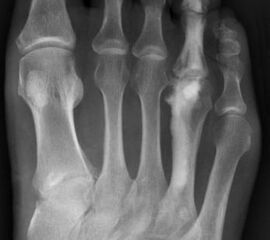

Das Enchondrom ist der häufigste Knochentumor im Bereich von Hand und Fuß und nach dem Osteochondrom der zweithäufigste gutartige Knochentumor überhaupt. Die geschlechtliche Verteilung ist ausgeglichen, Enchondrome finden sich meist bei Patienten zwischen 20-40 Jahren. Dieser chondrogene Tumor verhält sich meist asymptomatisch, kann aber durch eine Knochenexpansion und Schwellung sowie Spontanfrakturen (Abb. 17) auffallen. Radiologisch zeigen sich in der Regel gut abgrenzbare Osteolysen, Matrixverkalkungen sind typisch aber nicht obligat. Die MRT zeigt typischerweise eine annähernd flüssigkeitsäquivalente Signal­qualität mit niedrigen Signalintensitäten in T1 und hoher Signalgebung in T2, die Binnen­struktur weist eine für chondrogene Tumoren typische Lobulierung mit KM-Aufnahme auf.

Im Gegensatz zu Osteochondromen ist die Lage von Enchondromen nicht auf die Metaphyse beschränkt. Sie finden sich auch im Bereich der Epi- und Diaphysen. Die kurzen tubulären Knochen der Metatarsalia und Phalangen sind bevorzugt betroffen. Hier findet sich die Läsion typischerweise im Bereich der proximalen Phalangen oder distalen Metatarsalia, eine Ausbreitung auf die gesamte Diaphyse ist von hier aus jedoch nicht ungewöhnlich. Die Möglichkeit einer malignen Entartung (Chondrosarkom) ist im Bereich der Metatarsalia und Phalangen im Vergleich zu den langen Röhrenknochen und platten Knochen extrem selten 33. Die übliche Therapie besteht in einer gründlichen Curettage. Je nach Größe des Defekts und Schwächung der Kortikalis kann die Transplantation eines stabilisierenden kortiko­spongiösen Spans notwendig werden. Zusätzliche osteosynthetische Verfahren sind nur selten erforderlich.